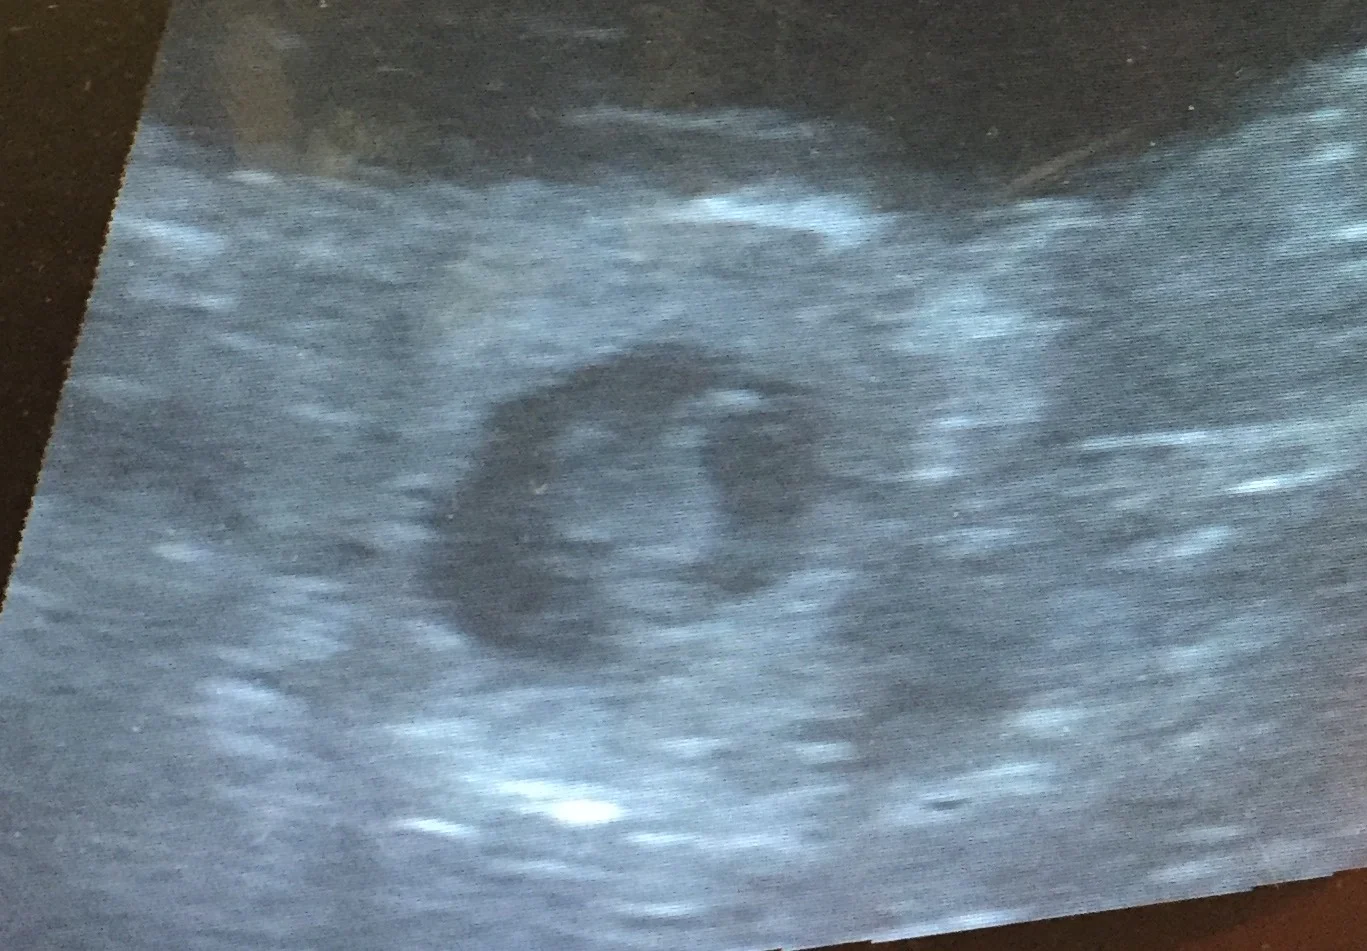

Heute ist der 39. Trächtigkeitstag und die Süße hat schon ein wenig zugenommen, das Bäuchlein wächst! Aber sehr selbst...